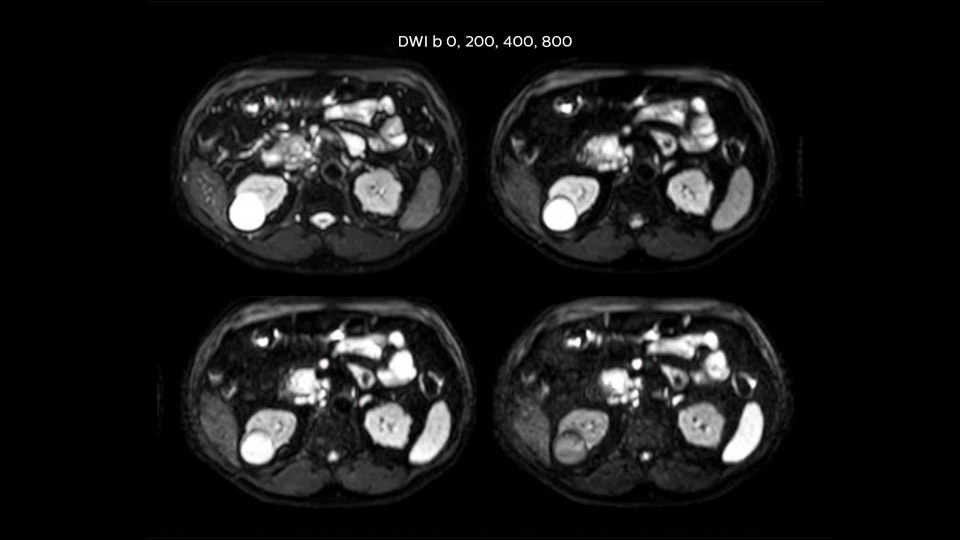

Dr. Baumann then implemented MultiVane XD for motion correction. It uses an extended reconstruction algorithm for imaging that is virtually motion free. “With MultiVane XD we get excellent motion-corrected images with high spatial resolution. We typically first optimize our scan for high image quality, and when satisfied with that, we try to reduce the scan time. So, we combined MultiVane XD with dS SENSE, which allows us to shorten the scan time,” he explains. “The performance of MultiVane XD in liver imaging is outstanding. MultiVane XD with dS SENSE is a powerful development in improving liver image quality.” “As we use breathhold imaging for T2-weighted liver scans, we depend on the patient’s ability to cooperate with the exam. This can present a real challenge when we are looking for small lesions, such as in our oncological patients. However, with MultiVane XD motion correction, we get excellent images. This is important for our surgeons, because they want to know exactly where the lesions are.”

“Our liver exams are quite fast,” says Dr. Baumann. “If the patient tolerates it, we use an arms-up position to reduce the FOV and speed up the exam with dS SENSE.” “We acquire one transversal high resolution T2-weighted sequence with 3 mm slice thickness, for example for pancreas or liver lesions. Then we also add a T2 fat suppressed MultiVane XD SPIR sequence. We perform these two routinely in our liver imaging. We use high dS SENSE factors to significantly shorten scan times to 2-4 minutes, which can improve our protocol; it’s a very robust scan.” “We include mDIXON for the dynamic sequences because of the robust and homogeneous fat suppression we get with that. We had been using eTHRIVE, but we are now quite happy with mDIXON. Sometimes we use a medication to calm the bowels, to further improve the image quality.”